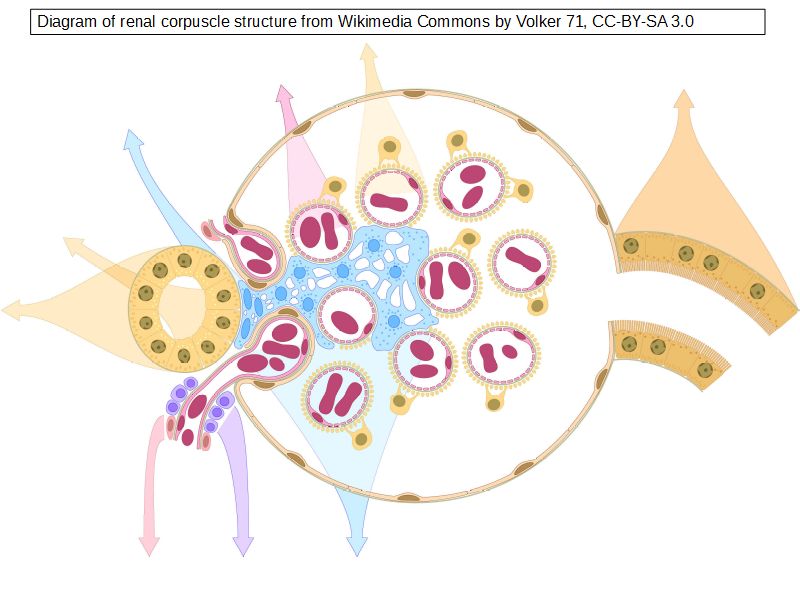

Renal corpuscle

- Tuft of capillaries

- grow into

- Blind end of nephron

- Several layers of epithelium

- Two sides

- Vascular pole

- Tubular pole

Epithelium layers

- Capillary endothelium

- Visceral layer of epithelium

- Podocytes

- Resting on glomerular basement membrane

- Capsular space

- Parietal layer of epithelium

- Simple squamous epithelium

Glomerular filtration barrier

- Three layers

- Fenestrated epithelium

- Exclude blood cells & platelets

- Glomerular basement membrane

- Main filtration barrier

- Thick

- Fused epithelial & endothelial BM

- Replenished by podocytes due to removal by mesangial cells

- Glomerular epithelium

- Through filtration slit

Capillaries

- Supported by

- Mesangial cells

- Mesangial matrix

- Phagocytic

- Maintain basement membrane

- Remove macromolecular deposits

Mesangial cells

- Around capillary loops at vascular pole

- Phagocytic

- Maintain basement membrane

- Remove macromolecular deposits

Podocytes

- Visceral layer of epithelium

- Protrude into capsular space

- Attached to basement membrane

- Long cytoplasmic extensions

- Primary processes

- Secondary processes

- Podocyte feet

- Tightly spaced

- Filtration slits 20 - 30 nm wide